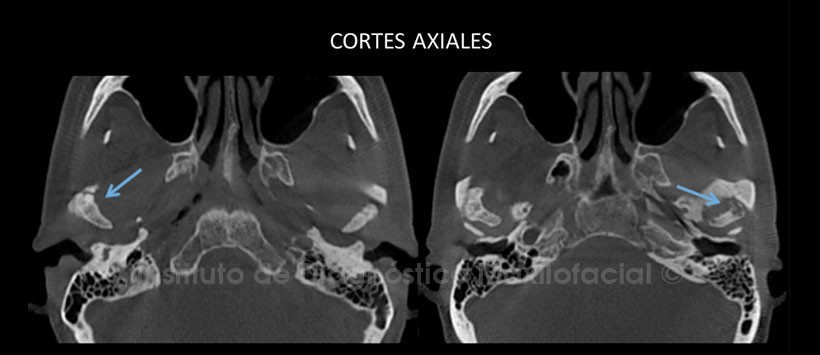

Al estudio mediante tomografía computarizada de haz cónico (CBCT), cortes axiales (Figura 2) y coronales (Figura 3) se evidencia alteración en la morfología y estructura de ambos cóndilos mandibulares con predominio del lado derecho donde apreciamos aplanamiento de las superficies condilares, formación de osteofitos y la presencia de cuerpos óseos libres proyectados a nivel sinovial. En el lado izquierdo podemos observar zonas de aplanamiento y erosión de corticales óseas. En ambos lados se aprecia disminución de los espacios discales.